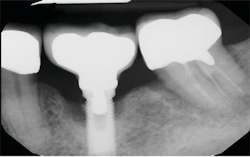

Symptoms of peri-implantitis may include bleeding on probing, deep probing depths, edema, redness, suppuration, and radiographic bone loss (figures 4 and 5).

One of the most perplexing causes of peri-implantitis is residual cement being left behind unknowingly. The cement is often difficult to feel with an explorer and not always visible radiographically. This happens often enough that the problem has earned its own name, “cementitis,” and it can create an infection severe enough to cause the implant to fail (figures 6–8).

Solutions to prevent retained cement include raising the restorative cement line, using only radiopaque implant cements, or using screw-retained implants.